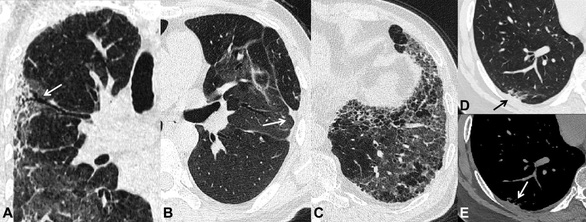

Những di chứng sau viêm phổi do SARS-CoV-2 được ghi nhận trên phim CT scan ngực sau 6 tháng theo dõi. A-dãn phế quản co kéo (mũi tên). B- xẹp phổi dạng đường (mũi tên). C- xơ phổi dạng tổ ong. D và E- dày màng phổi tạng (mũi tên)

Trên phim chụp CT scan ngực, hình ảnh xơ hóa phổi biểu hiện dưới nhiều dạng và mức độ như: hình ảnh dải xơ, dày các vách liên tiểu thùy, hình ảnh lưới, dãn phế quản co kéo và điển hình nhất là hình ảnh tổ ong